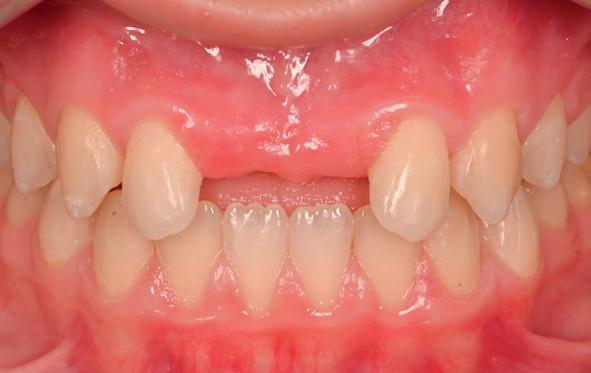

Esthetiek in de tandheelkunde, met name in het front, is een samenspel tussen de roze zachte weefsels en de witte harde weefsels. In het Engels wordt dit ook wel aangeduid met “pink and white esthetics”, waarbij het verkrijgen van correcte pink esthetics over het algemeen een grotere uitdaging vormt dan de white esthetics. Deze roze esthetiek is vooral van belang bij gebitselementen waarbij sprake is van recessie (het terugtrekken van de gingivalijn, waardoor de radix en een langere tand zichtbaar worden). De situatie wordt nog uitdagender wanneer een tand of kies niet is aangelegd, of in het verleden is verwijderd. Het element zorgt er immers voor dat de gingiva rondom de natuurlijke kroon ligt en dat er voldoende weefseldikte rondom deze kroon aanwezig is. Als het element ontbreekt, groeit het alveolaire bot dicht, omdat er geen radix meer is, en daarmee ook de mucosa (wanneer er geen element meer aanwezig is, spreken we niet meer van gingiva maar van mucosa), die dan afgevlakt is. De papillen tussen de afwezige elementen vlakken dan ook af.

Om één of meer afwezige elementen te herstellen bij een vaste voorziening, kan er een etsbrug of kunnen er implantaten worden geplaatst. De esthetiek valt of staat hierbij met de aanvulling van de zachte weefsels, zowel in de vorm van verbreding hiervan als het creëren van een zogenoemd emergence profile –dat wil zeggen dat de tand op een natuurlijk ogende wijze vanuit het tandvlees tevoorschijn moet komen.

Een gezonde, jonge dame had op 8-jarige leeftijd een trauma op school waarbij ze op haar voortanden was gevallen. Volgens haar moeder waren deze voortanden tot onder het tandvlees afgebroken. Nadat ze

via de spoeddienst bij de kaakchirurg terechtkwam, werd daar besloten tot extractie van de 11 en 21. In de opinie van de auteur is dit een te voorbarige behandeling geweest; de kans dat beide centrale incisieven bij een meisje van 8 jaar na een val zodanig beschadigd zijn dat de radices zonder kans op behoud verwijderd moesten worden, is bijzonder klein. Helaas was het kwaad al geschied.

Op 16-jarige leeftijd werd de patiënt door haar behandelend orthodontist naar de auteur verwezen voor een restauratieve oplossing voor de afwezige 11 en 21. In de tussenliggende periode had patiënt een retainer gedragen met twee kunststof tanden (afbeelding 1). Zowel de patiënt als haar moeder hadden een sterke voorkeur voor een implantaat gedragen vaste oplossing. Gezien haar jonge leeftijd was dit echter nog geen optie, omdat er nog verticale groei te verwachten viel. Implanteren op jonge leeftijd – dat wil zeggen vóór het 21e levensjaar – kan resulteren in een infrapositie van het implantaat, omdat de rest van het gebit nog verticaal kan doorgroeien.

Middels shared decision making werd het volgende plan overeengekomen: eerst zou er een etsbrug met vleugels op de 12 en 22 worden vervaardigd, om op 21-jarige leeftijd verder te gaan met implantologie.

Bij klinisch en röntgenologisch onderzoek viel echter op dat radix van de 12 en 22 een convergerende (de radices staan dan naar mesiaal en naar elkaar toe) in plaats van divergerende (radices staan dan van elkaar af) stand had. Door deze convergerende stand van de radices was er in mesio-distale zin geen ruimte voor twee implantaten ter plaatse van de 11 en 21. Er werd daarom besloten, in tegenzin

van de patiënt, om eerst weer vaste apparatuur terug te plaatsen om de radices in een divergerende stand te plaatsen. Gelukkig verliep deze behandeling voorspoedig. (afbeelding 2 -4). Het volgende behandelplan werd gemaakt: